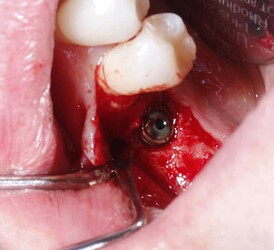

Buccal bone missing after implant placement

(preoperative picture for LL6), LL6 was extracted about 10 weeks before implant placement

(buccal wall thickness is adequate right after implant)